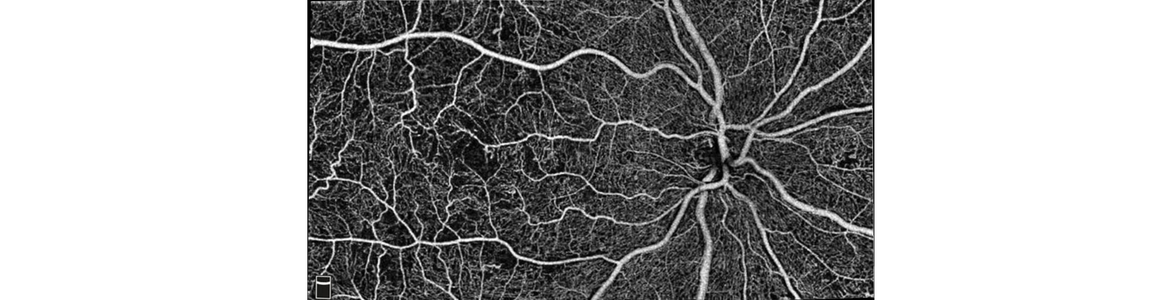

DRI-OCT Triton Plus OCT-Angio